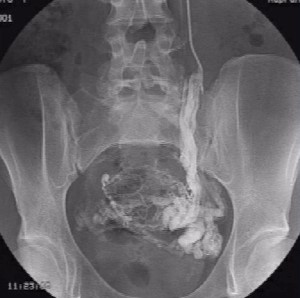

Примечательно, что абсолютно верную и точную информацию о наличии заболевания, состоянии вен малого таза на финальном этапе обследования помогает получить проведение инвазивного рентгеноконтрастного исследования. Во время селективной оварикографии и тазовой флебографии врачи уточняют анатомические особенности положения, строения яичниковых сосудов, их диаметр, выявляют количество и характер притоков гонадных сосудов, наличие рефлюкса, свойственного внутренним и яичниковым подвздошным венам, а также связь подкожных и сосудов малого таза.